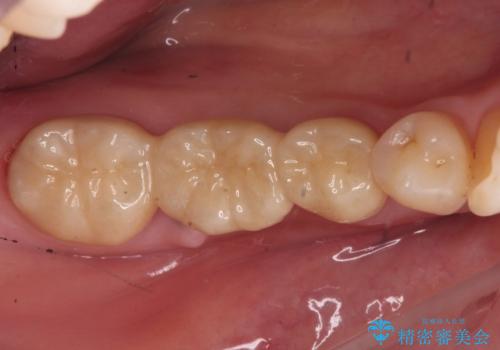

歯がなくなったところに関しては、ブリッジで修復することにしました。

- 26.2万円(ヴェレッツァクラウン 7.7万円×3本 仮歯 1.1万円×3本)費用は治療当時の料金となります